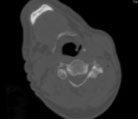

Periradikuläre Injektion Lendenwirbelsäule (Spritze an die Nervenwurzel unter CT-Kontrolle)

Genaue Positionierung der Nadel im engen Hüftgelenkspalt mit knöchernen Überbauten, sehr adipöser Patient, lange Injektionsstrecke durch den Körper (CT-Aufsicht/Hüfte)

Die Nadel liegt im Gelenk am Hüftkopf (CT-Querschnitt/Becken)